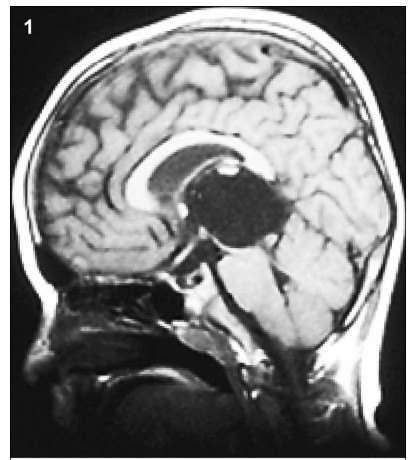

1 Case presentation 1.1 History A space-occupied cystic lesion in the rear of the third ventricle was detected in an 8-year-old boy presenting with symptoms of raised intracranial pressure (ICP) and a diagnosis of “cystic lesion” 3 years ago (Figure 1). He underwent a ventricle-peritoneal shunt operation without serum tumor marker test and became asymptomatic soon after the operation. Intermittent regular brain Magnetic Resonance Imaging (MRI) demonstrated no evidence of massive aggrandizement during the following 2 years. Then, 2 months ago,he rapidly developed unsteady gait and confined ocular motor function,followed by acute aggravating clinical symptoms. MRI scans showed that the mass had remarkably enlarged in size and the solid component had become predominant,instead of the prior cystic lesion. Furthermore,the transitional parenchyma tumor was heterogeneously and notably enhanced in contrast-enhanced MR image (Figure 2).

Figure 1 The MRI (2013) showed a cystic lesion in the rear of third ventricle.